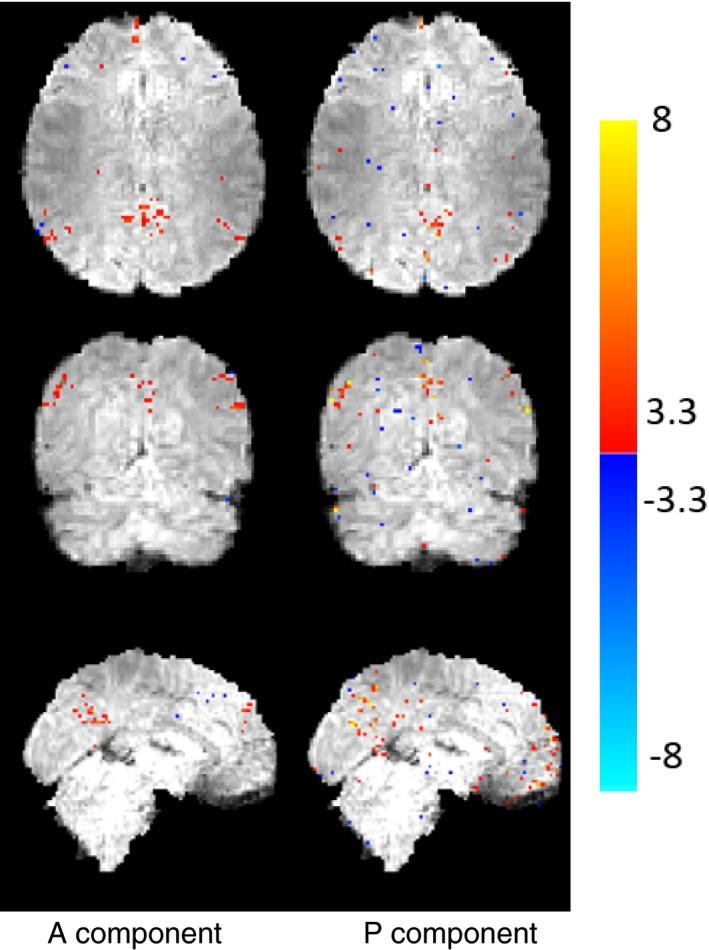

The proposed approach decomposes the fMRI signal into a component which has a fixed rank and a component consisting of a sum of periodic signals which is sparse in the temporal Fourier domain. Data reconstruction is performed by solving a constrained problem that enforces a fixed, moderate rank on one of the components, and a limited number of temporal frequencies on the other. Our approach is coined PEAR - PEriodic And fixed Rank separation for fast fMRI.

Experimental results include purely synthetic simulation, a simulation with real timecourses and retrospective undersampling of a real fMRI dataset. Evaluation was performed both quantitatively and visually versus ground truth, comparing PEAR to two additional recent methods for fMRI reconstruction from undersampled measurements. Results demonstrate PEAR's improvement in estimating the timecourses and activation maps versus the methods compared against at acceleration ratios of R = 8,10.66 (for simulated data) and R = 6.66,10 (for real data).

结果

实验结果包括纯粹的合成模拟、具有真实时间序列的模拟以及对真实 fMRI 数据集的回顾性欠采样。通过与真实数据进行比较,对基于地面真值的定量和视觉评估,将 PEAR 与另外两种用于从欠采样测量中重建 fMRI 的最新方法进行了比较。结果表明,PEAR 在估计时间序列和激活图方面的性能优于所比较的方法,在加速比为 R=8、10.66(模拟数据)和 R=6.66、10(真实数据)时。